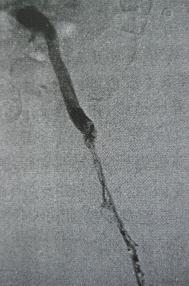

以下是下腔静脉滤器置入及左下肢深静脉置管溶栓术治疗前后对比图

左下肢深静脉置管溶栓术前 左下肢深静脉置管溶栓术后